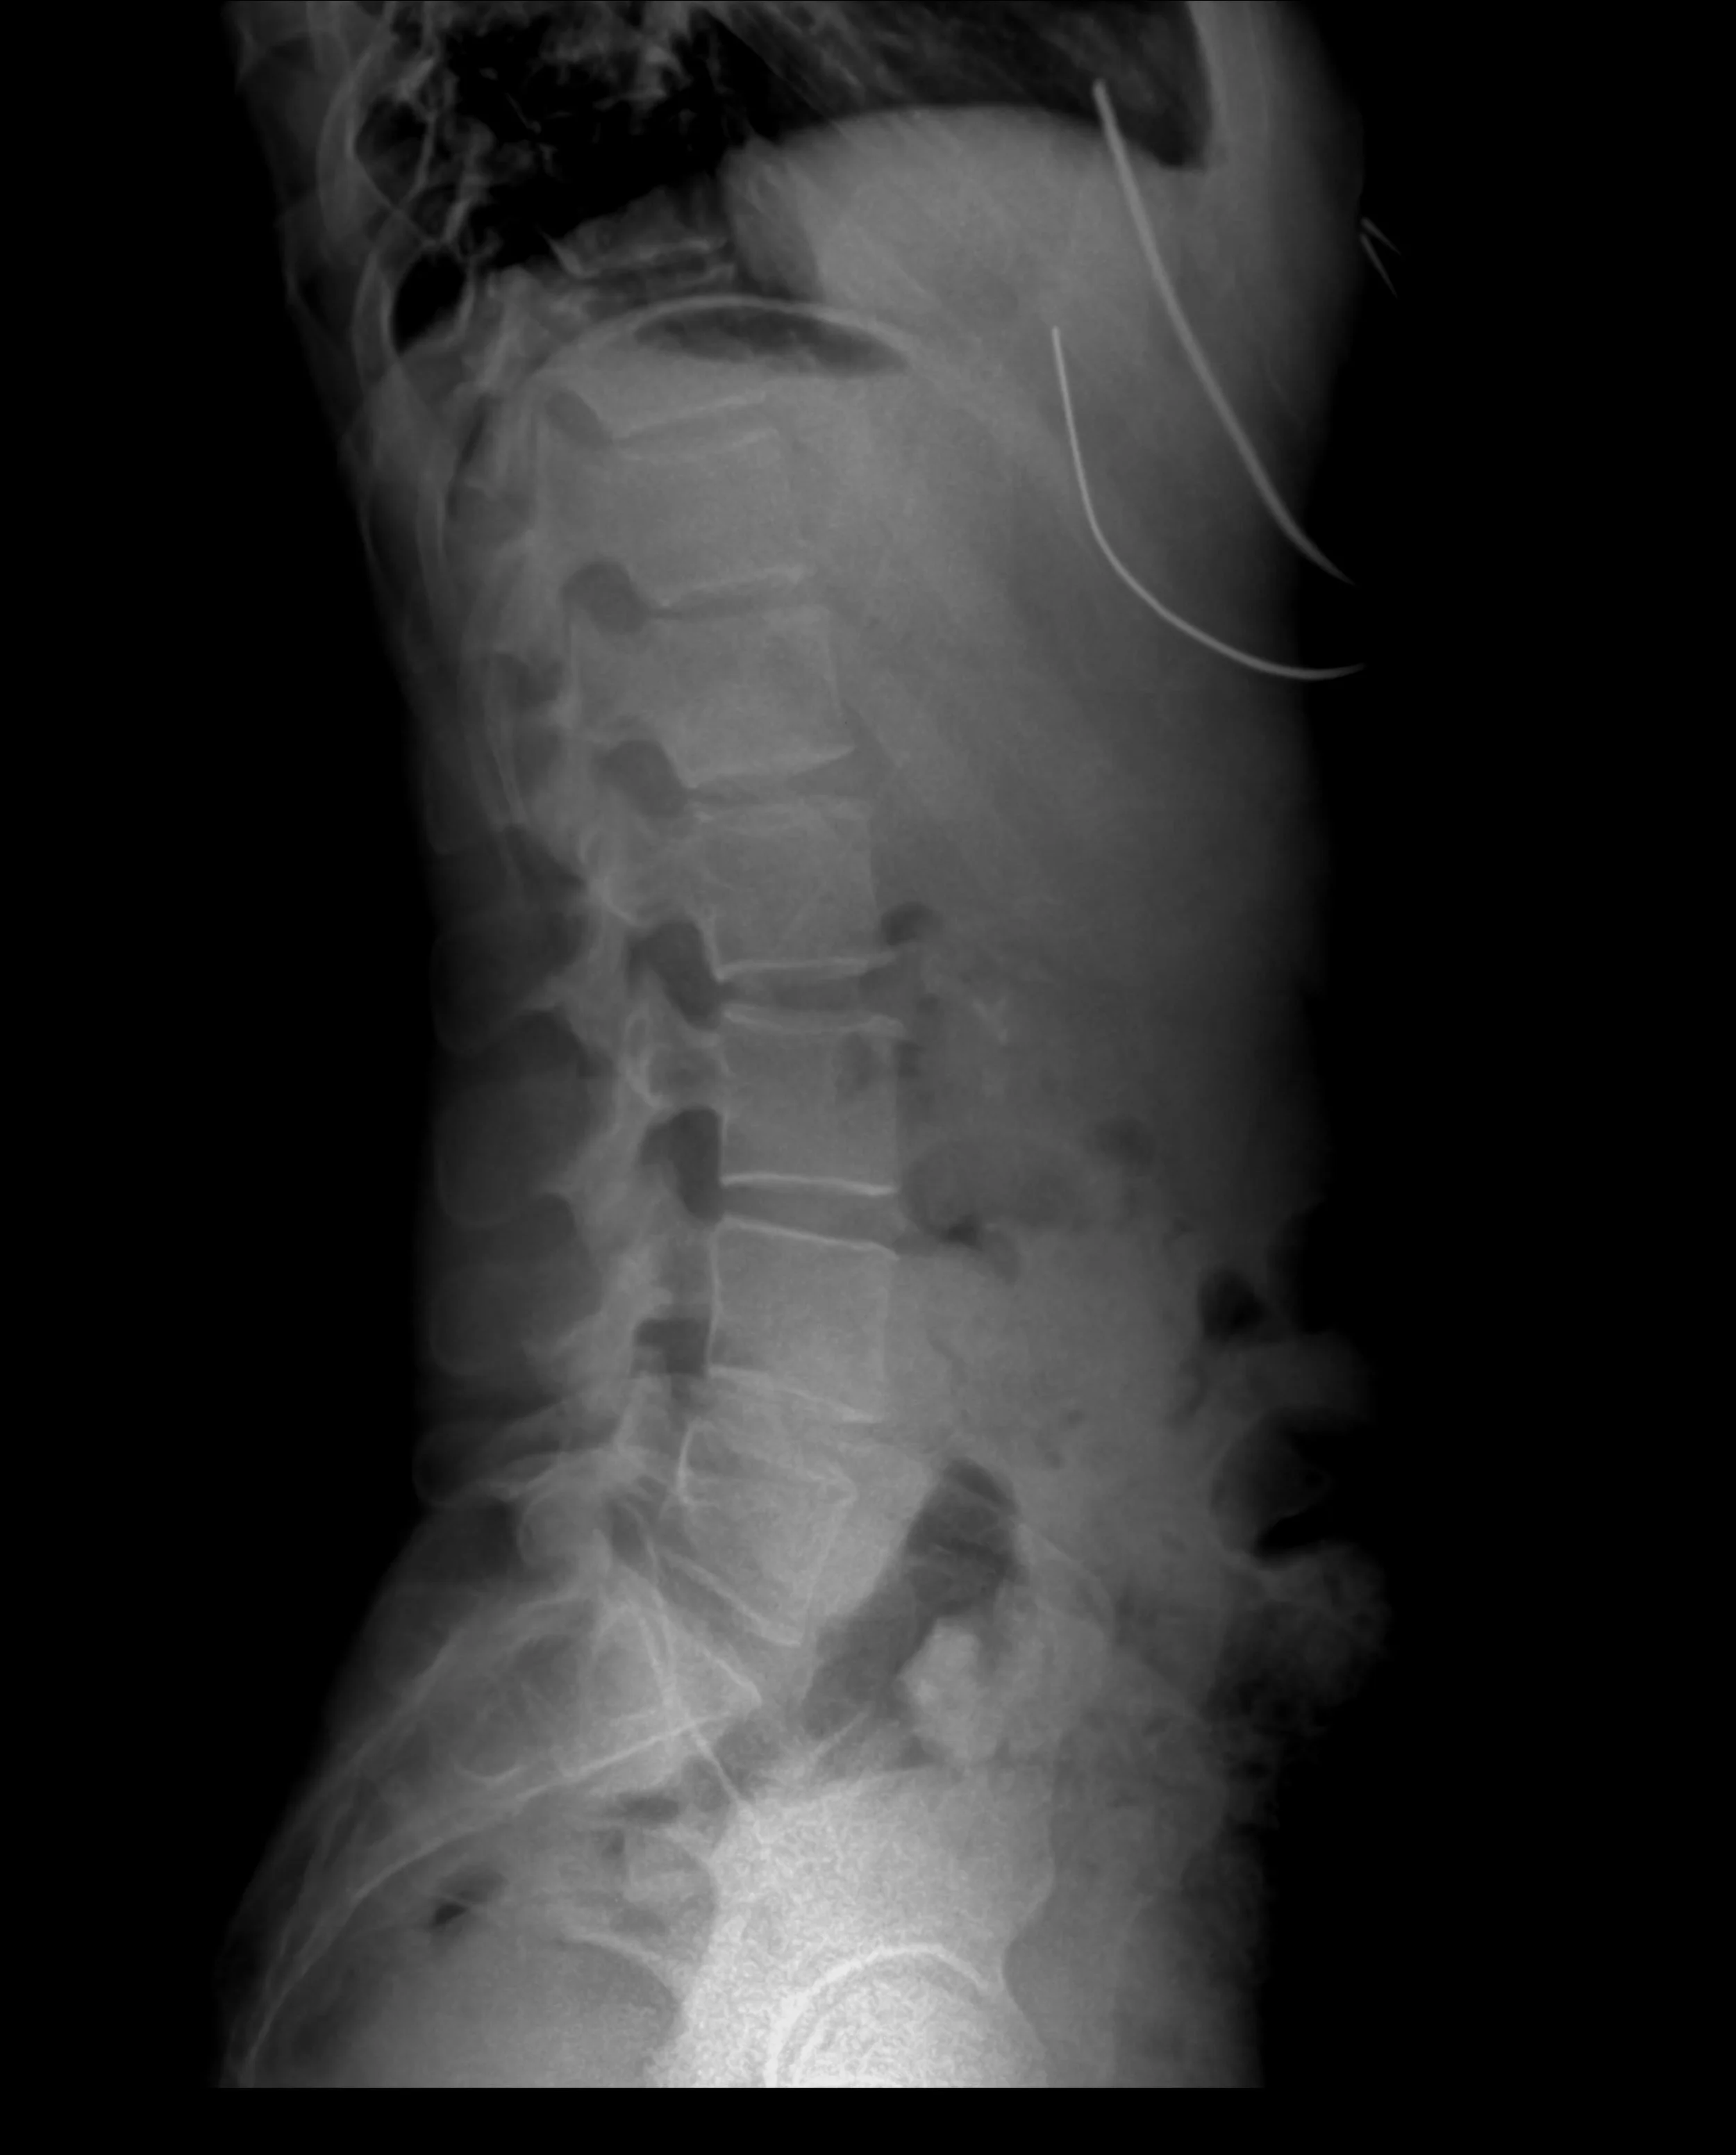

• Il mal di schiena e il dolore al collo sono tra i disturbi muscolo-scheletrici più frequenti, ma spesso vengono trattati senza approfondire le vere cause. Se il dolore torna, significa che qualcosa nel movimento, nella gestione del carico o nello stile di vita continua ad alimentarlo.